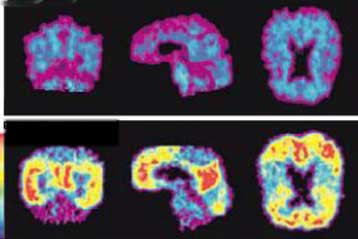

Η αύξηση του μέσου όρου ζωής στις αναπτυγμένες και κυρίως, στις υπό ανάπτυξη χώρες, έχει ως αποτέλεσμα και την αύξη ση της συχνότητας εμφάνισης των παθήσεων της τρίτης ηλικίας, όπως η υπέρταση, η στεφανιαία νόσος, τα αγγειακά εγκεφαλικά επεισόδια και οι άνοιες.